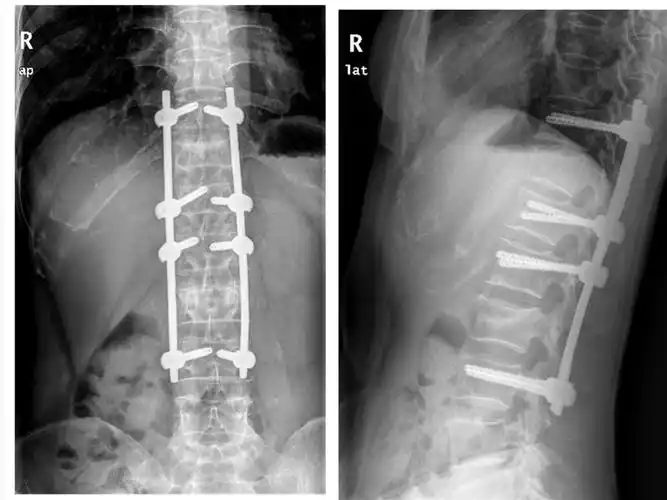

椎弓根螺钉内固定术

我院成功开展经皮脊柱椎弓根钉内固定手术